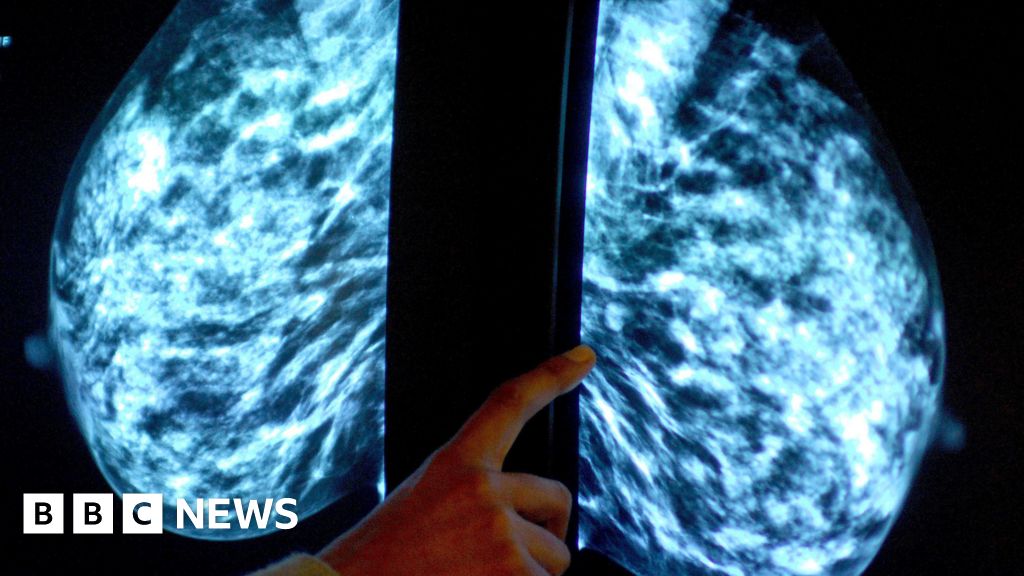

PA MediaPeople are being asked to have their say on plans to improve vaccination and screening services on the Isle of Man.

A four-week consultation has been launched by Public Health, which would inform a new strategy for routine procedures.

Public Health said it would help to understand perceptions of the services, where they are provided, and barriers that people have in accessing them.